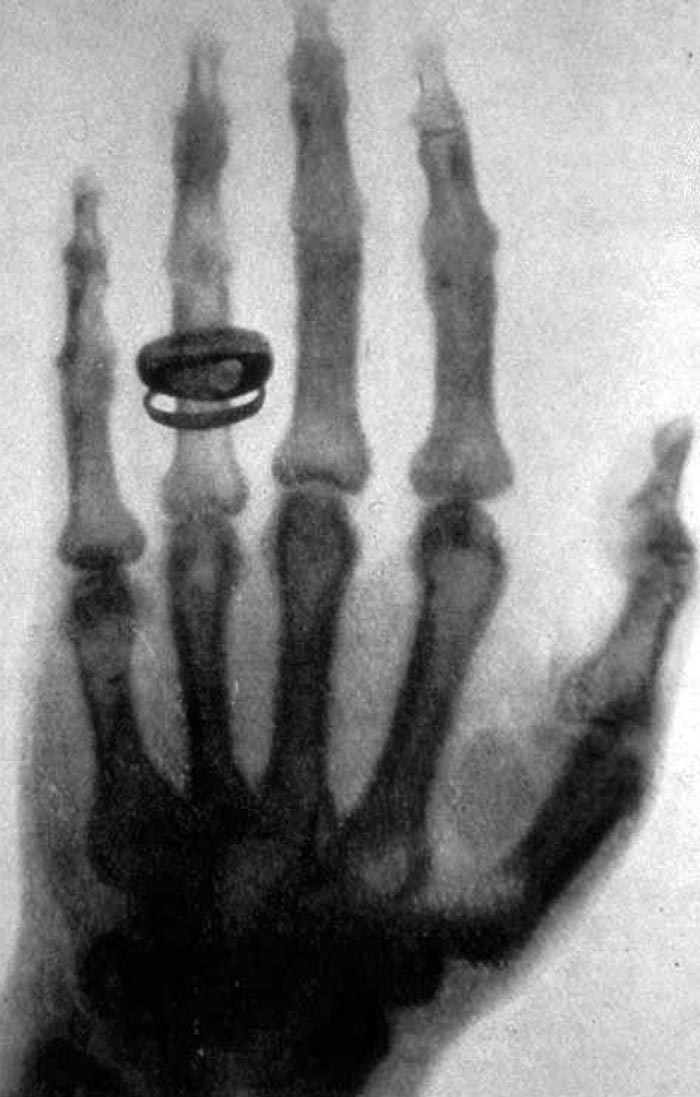

Рентгеновские лучи

В 1895 году немецкий физик Вильгельм Конрад Рентген открыл X-лучи, позволявшие буквально «просвечивать» человеческий организм, выявляя дефекты костей и появление злокачественных образований. Он не стал патентовать свое открытие, позволив использовать рентгеновское излучение в медицине и различных отраслях промышленности.

Сегодня рентгеновские лучи помогают своевременно выявить туберкулез, раковые новообразования, повсеместно используются в травматологии и хирургии, а также являются главными элементами УЗИ.